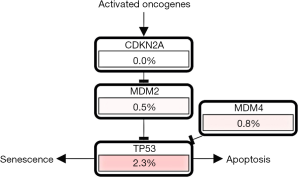

Different mutation types may have distinct biological functions in various cancers, and the co-expression of genes may also affect gene functions. Using the cBioPortal database, we explored the location and types of mutation, as well as co-expression, among genes related to the TP53 signaling pathway. Among these genes, TP53 (2.3%) was the most frequently aberrant gene in WT, followed by MDM4 (0.8%), and then MDM2 and TP53BP1 (0.2%). The most common types of mutation in TP53 were missense and deep deception, while amplification was the most common mutation in MDM2, MDM4, and TP53BP1 (Figure 3A,B). The three-dimensional structure of TP53 is shown in Figure 3C.